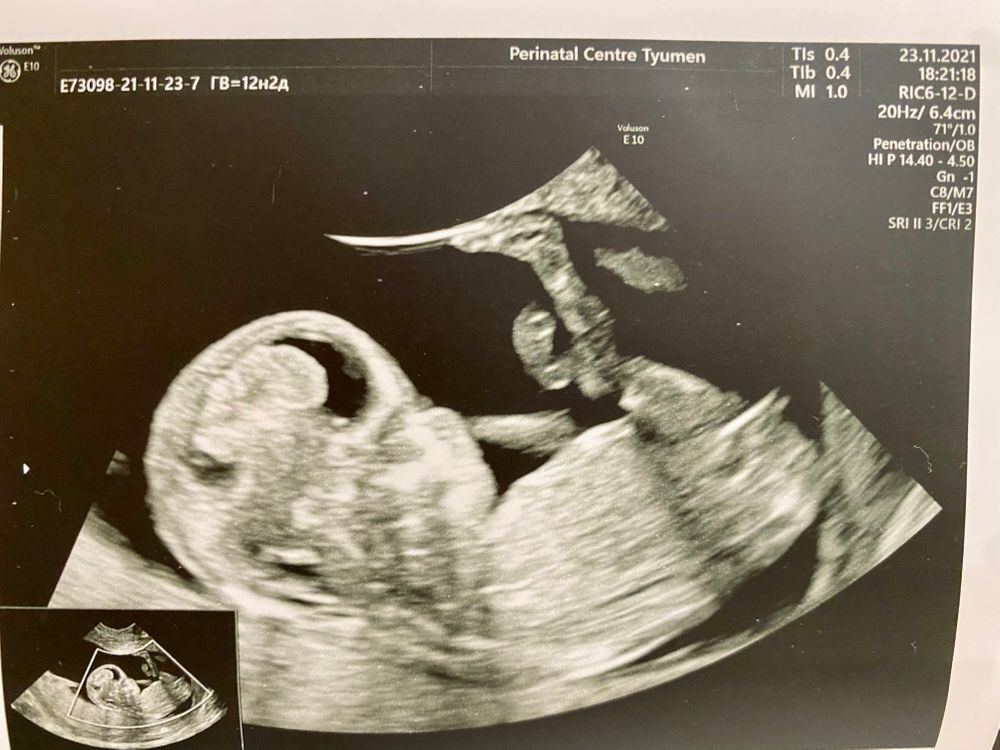

Девочки, привет. Врач на УЗИ пол не сказала, говорит «немного сомневаюсь, а это все-таки +700 рублей стоит» 😂 Кто что видит?) Интересно так 🤪

Если на послебнем фото показан половой уголок, то похоже на девочку)

Сомневалась ,наверное,так как ,как по мне ,по очертаниям черепа на мальчика похож . А если это половой бугорок на фото, то наклон на девочку.